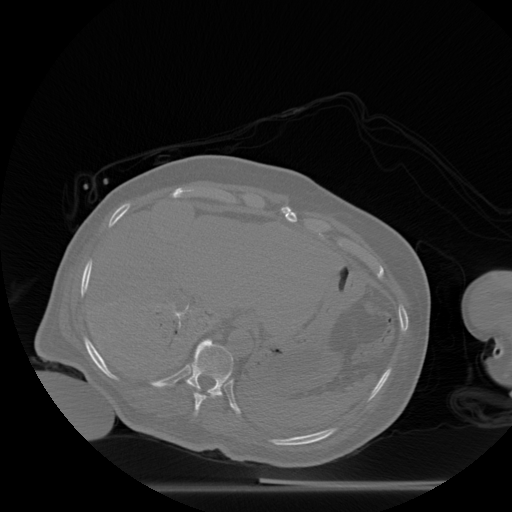

Figure 3: Radio-frequency ablation dataset. (a) through (g): one of the slices (512 x 512) from each of the 8 scan volumes of a longitudinal study dataset of the liver. Note that in volumes (a) through (g), the needle (shown in red in (f)) approaches the target tumor. (h) the organ after the ablation: this slice is displayed on a separate intensity scale to enable proper viewing of the region marked in green that shows the after-effects of ablating the tumor.

The dataset from this longitudinal medical study consists of 8 scans taken during the ablation procedure. We demonstrate our method for 2D reconstruction by choosing a single slice from each of the 8 volumes as our dataset. Note that all these 8 slices are located at the same index 222The notion of same index (slice number corresponding to the same depth) makes sense in the context, because in such problems, the different scans are aligned with each other. within each of the respective volumes. Fig. 3 shows the chosen set of 2D slices (each of size 512×512512512512\times 512) from the different volumes. Observe that the needle is seen in all of the first 7 slices and the effect of ablation is seen in the 8th slice.